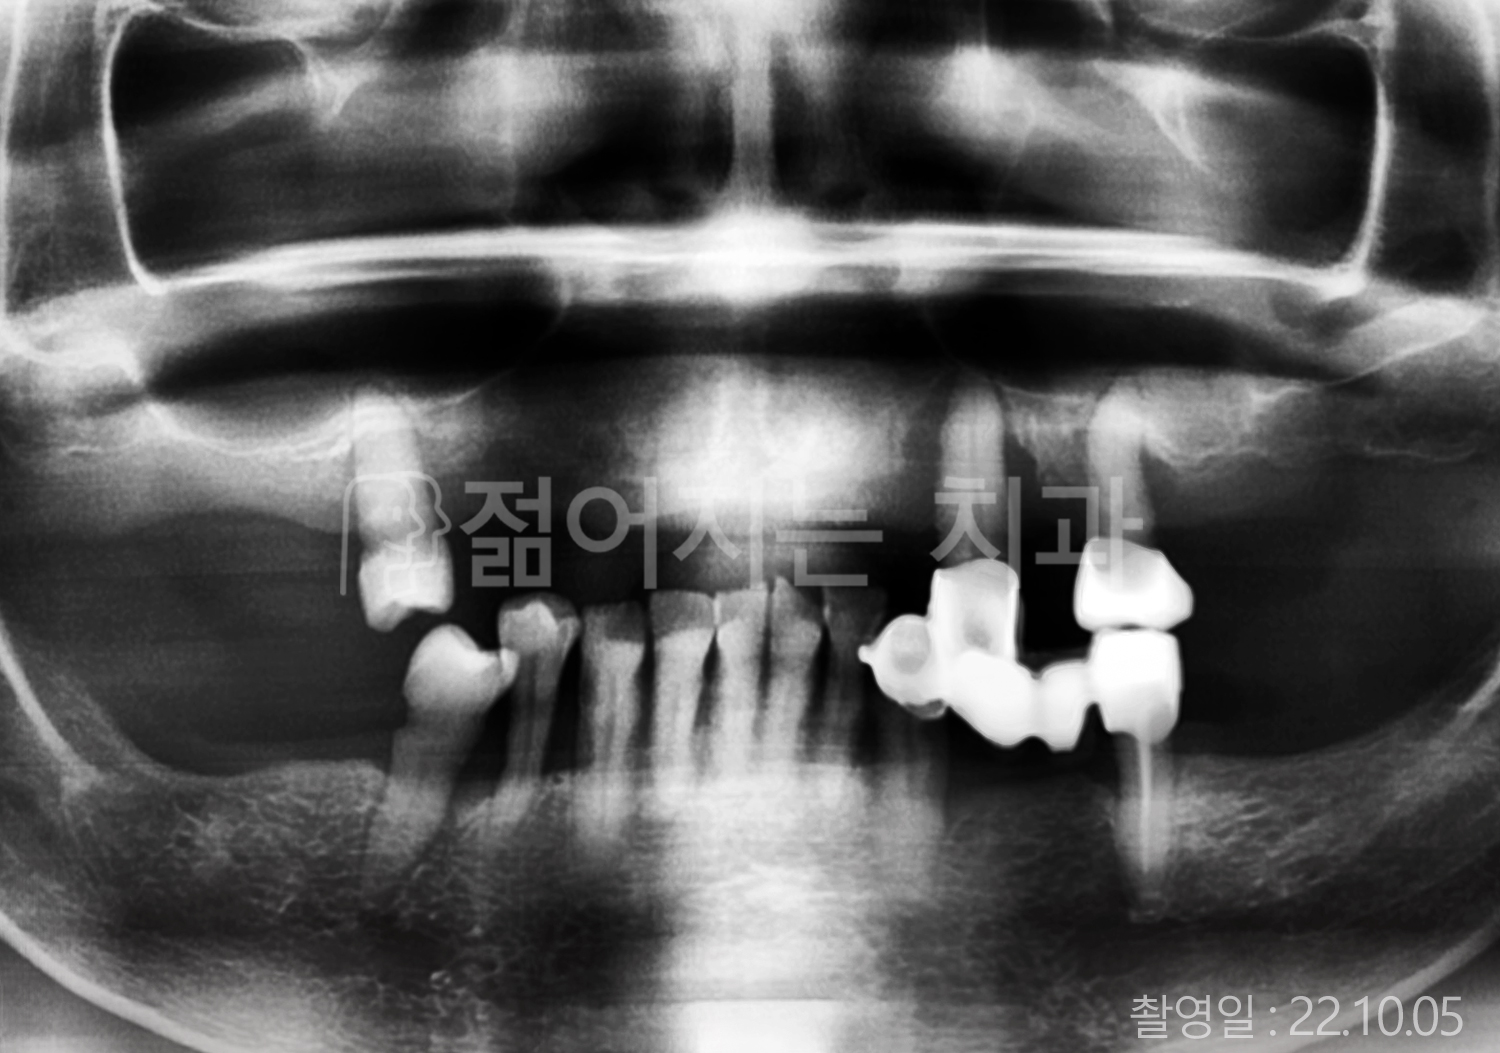

• 50대 고혈압, 당뇨, 고지혈증 전체치아 10개 이상 임플란트

• 60대 골다골증, 간경화 전체치아 10개 이상 임플란트

• 60대 고혈압, 고지혈증 전체치아 10개 이상 임플란트

• 50대 고혈압, 당뇨 전체치아 10개 이상 임플란트

• 60대 고혈압 전체치아 10개 이상 임플란트

• 60대 전체치아 10개 이상 임플란트

• 60대 고지혈증 전체치아 10개 이상 임플란트

• 40대 전체치아 10개 이상 임플란트

• 70대 전체치아 10개 이상 임플란트